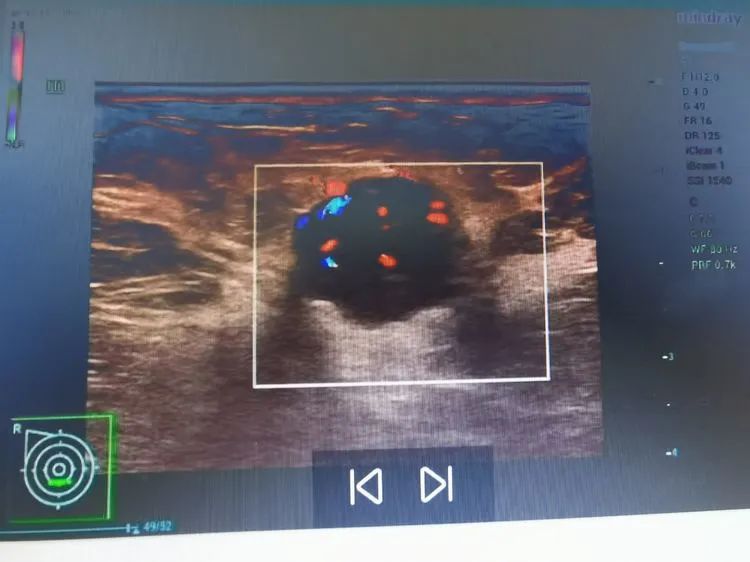

故事发生在数月前,刚刚50岁出头的陈女士在一次体检中,意外发现右侧乳腺包块。虽然包块不疼不痒也不大,但是为了明确性质,陈女士和家人来到广济医院做进一步检查。安静的彩超室里,随着探头的游走,段林主任仔细捕捉着屏幕上每一处变化,经验丰富的她很快发现了异常。仔细辨别后,她截取典型病变的画面后,给出超声诊断:右乳实性低回声结节22*16*16mm,BI-RADS4b类,右侧腋窝多发低回声结节。随后,段主任将彩超影像的诊断结果告知家人和接诊科室,建议进一步检查。得知诊断结果,陈女士一家人心中五味杂陈。

原来,超声诊断上的“BI-RADS4b”代表着“不太好”。专家解释道,乳腺BI-RADS分级是根据肿物的大小、边界是否光滑、肿物内是否有血运、钙化及同侧的腋窝是否出现异常肿大的淋巴结进行的分类。一共分0-6七个等级。0-3级,绝大多数是良性病变,4级有一定恶变的可能。4级中又分为4a、4b、4c三个亚级,恶性程度逐渐增加,恶性危险性3%—94%。5-6级基本属于恶性,要积极进行手术切除,并配合术后的综合疗法,提高肿瘤的治疗效果。